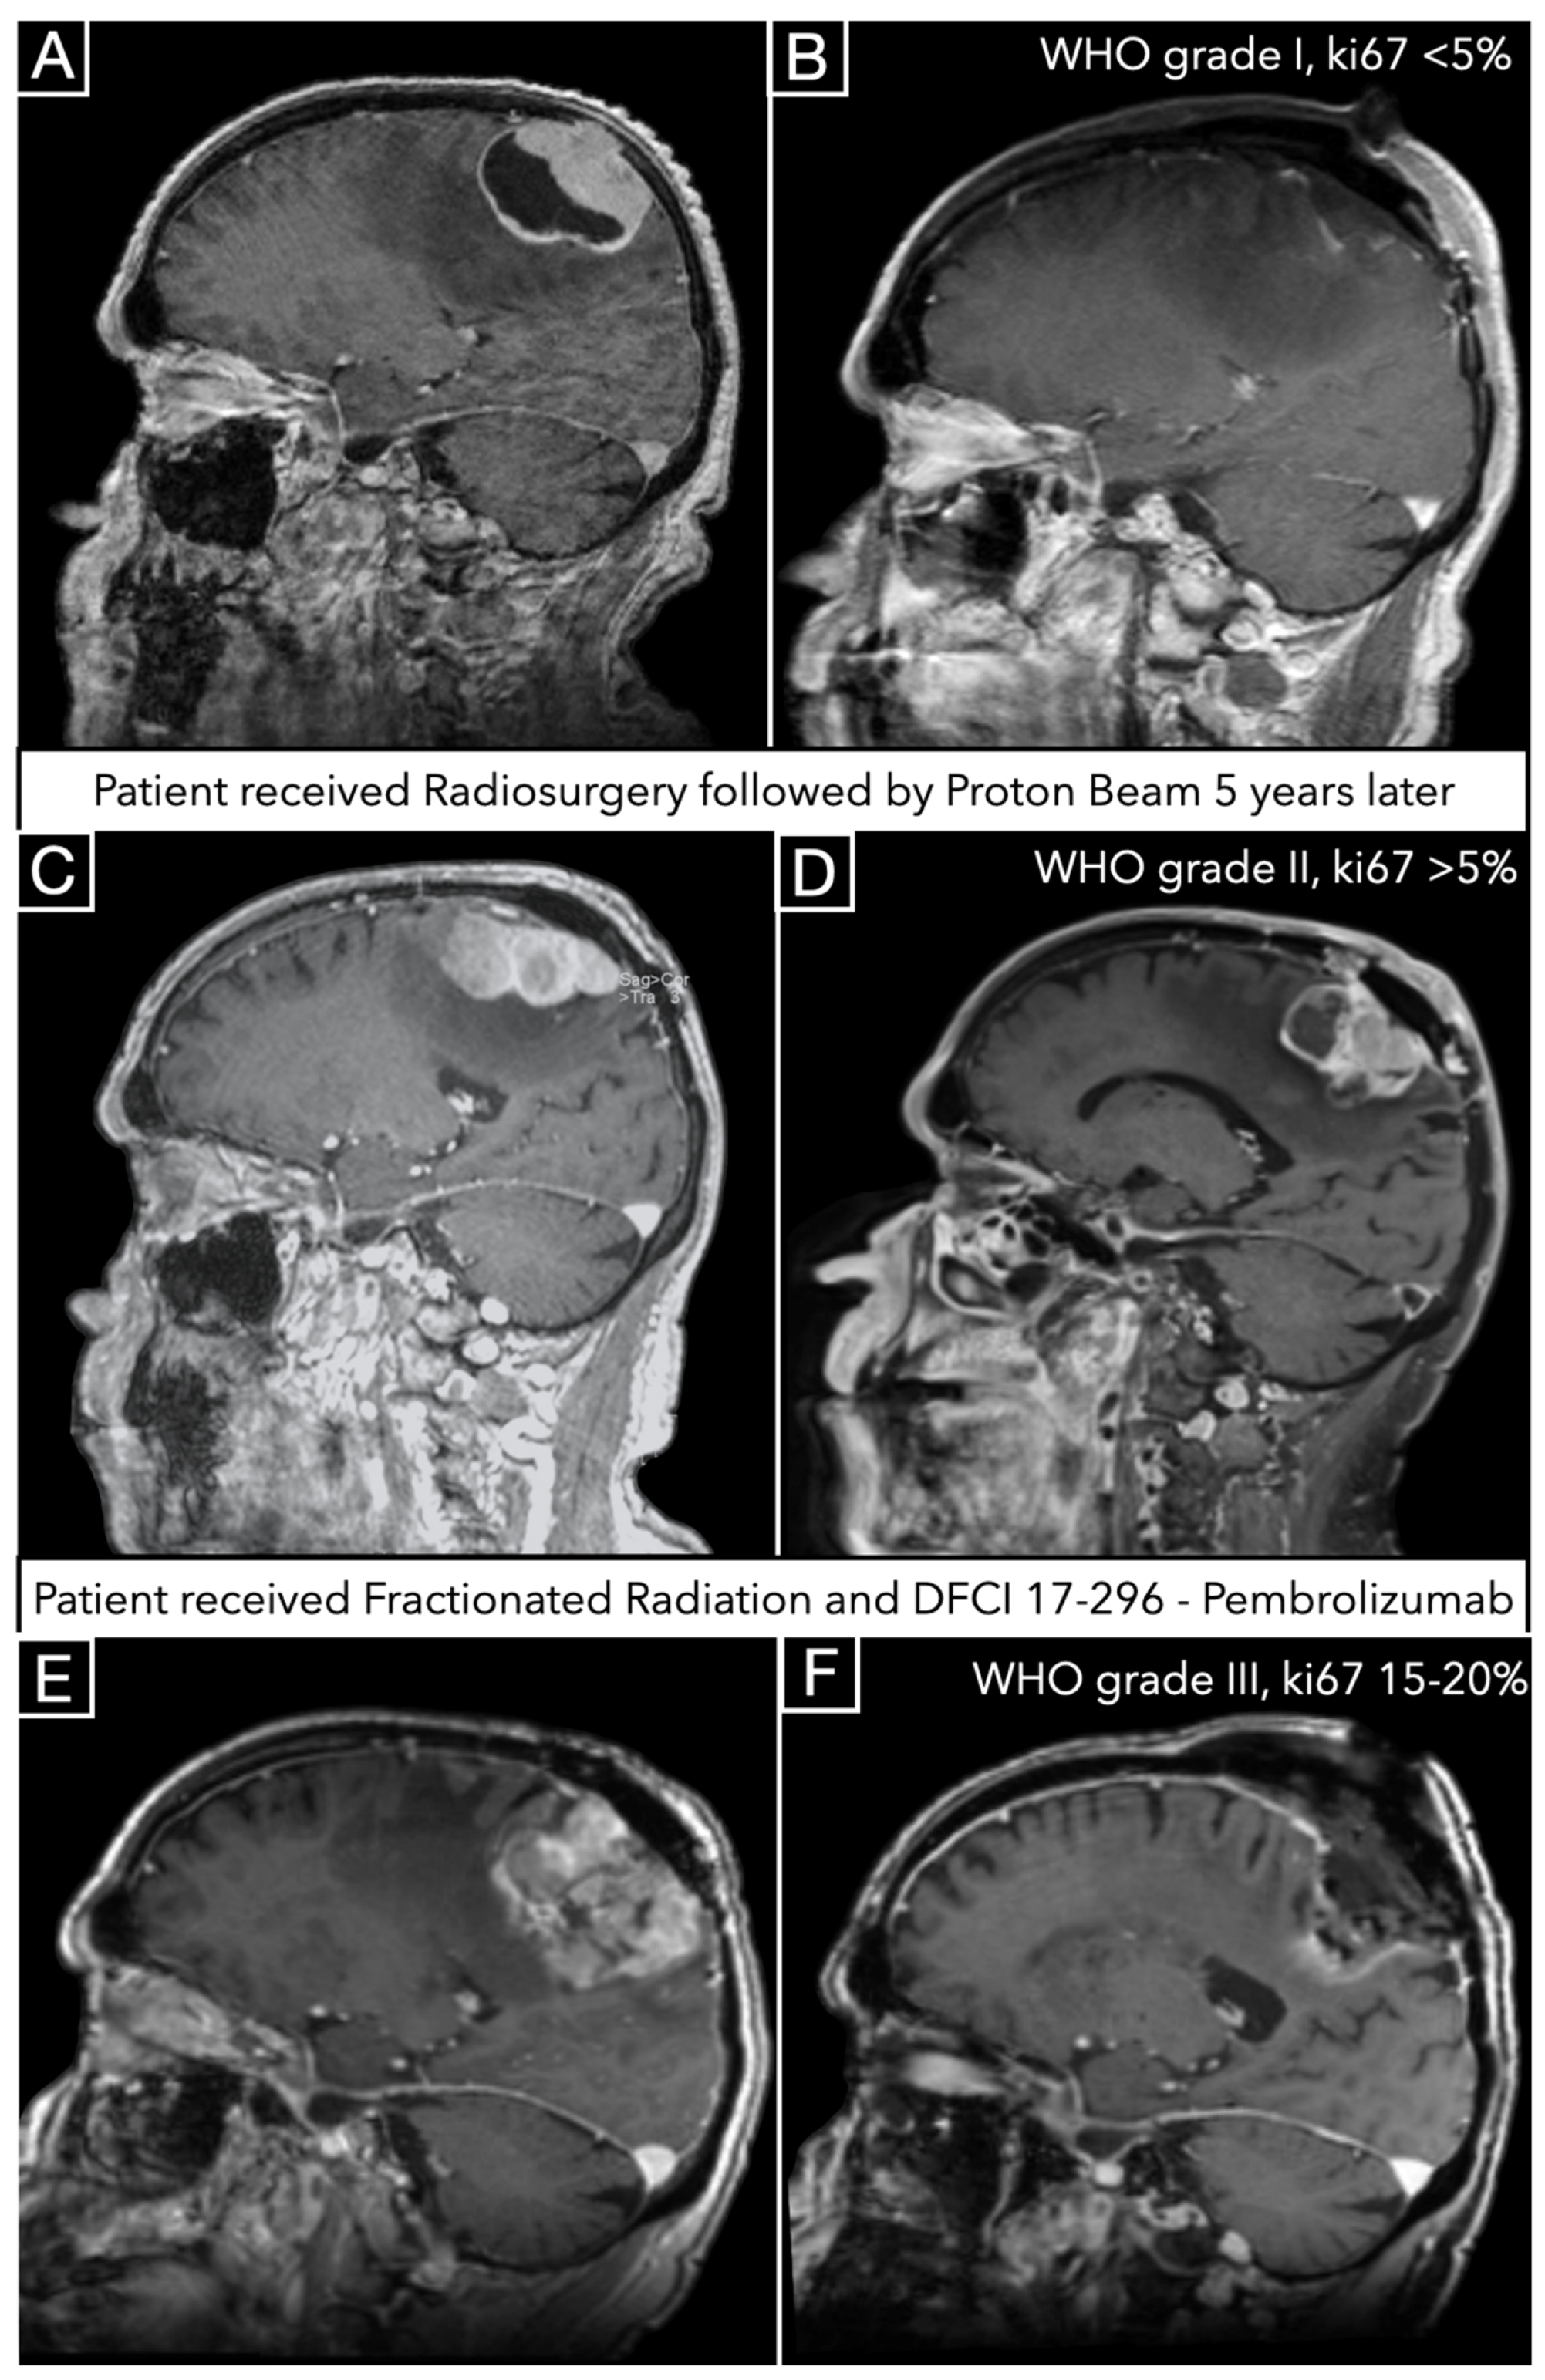

3.5. Illustrative Case

4.5. Malignant Progression